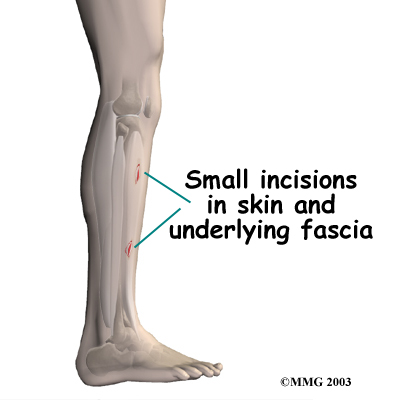

Surgery

Surgery is rarely needed to correct problems of shin splints. However, shin splints that are complicated by compartment syndrome may require surgery, sometimes immediately.

If compartment syndrome is discovered and diagnostic tests show high pressures within the tissues of the lower leg, surgery may be recommended right away. The procedure to remove the pressure is called fasciotomy. Fascia is the connective tissue around and between muscles and organs. The surgeon makes a fewon either side of the lower leg. The nearby layer of fascia within several compartments is cut and removed to reduce the pressure within the compartment. The incisions are left open at first. Tissue pressures are checked over a period of two to three days. The wounds are then closed.

If compartment syndrome is discovered and diagnostic tests show high pressures within the tissues of the lower leg, surgery may be recommended right away. The procedure to remove the pressure is called fasciotomy. Fascia is the connective tissue around and between muscles and organs. The surgeon makes a fewon either side of the lower leg. The nearby layer of fascia within several compartments is cut and removed to reduce the pressure within the compartment. The incisions are left open at first. Tissue pressures are checked over a period of two to three days. The wounds are then closed.

If the problem has been present for more than three months, the surgeon may only need to make one or two incisions to cut the layer of fascia and reduce pressure inside a single problem compartment.